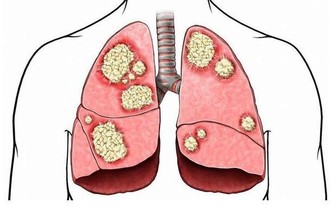

首先是孩子長高的原理,孩子長高其實就是將骨骼拉長,

所以媽媽們就要想辦法讓孩子的骨骼發育長長。

而骨骼的發育就少不了鈣的吸收,所以長高的前提是補鈣。